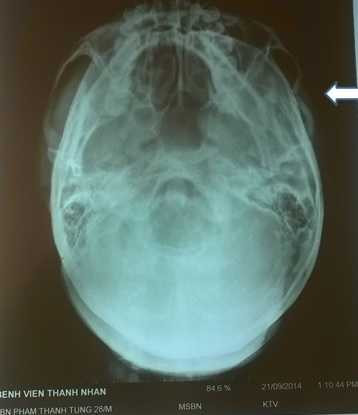

| X quang để tìm phần xương bị tổn thương của bác sỹ Phạm Thanh Tùng. |